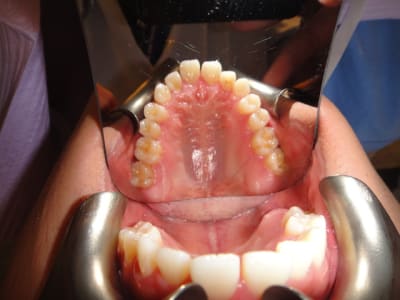

Patient asiatique, 25 ans, consulte car il veut corriger son crossbite bite antérieur localisé aux latérales et son crossbite secteur 2/3. Il aimerait également corriger son apparence générale, son profil notamment.

Ci joints photos, ceph, modeles.

il y'a une forte compensation alveolaire maxillaire superieure anterieurement et lateralement,

pour l'option chirurgicale je voudrais savoir pourquoi on a proposé l'extraction des 2 1eres premolaires vu quon a déja 2 dents manquantes au maxillaire superieur (3emes molaires),

je proposerai plutot un simple alignement et decompensation alveolo-dentaire sans extraction suivi de chirurgie orthognatique dexpansion maxillaire et de recul mandibulaire +/- avancée maxillaire (les deplacements des pieces osseuses dependent de notre diagnostic cephalometrique dans le sens sagittal)et extraction de 3emes molaires mandibulaires pour pouvoir coordonner les 2 arcades avec le meme nombre de dents.